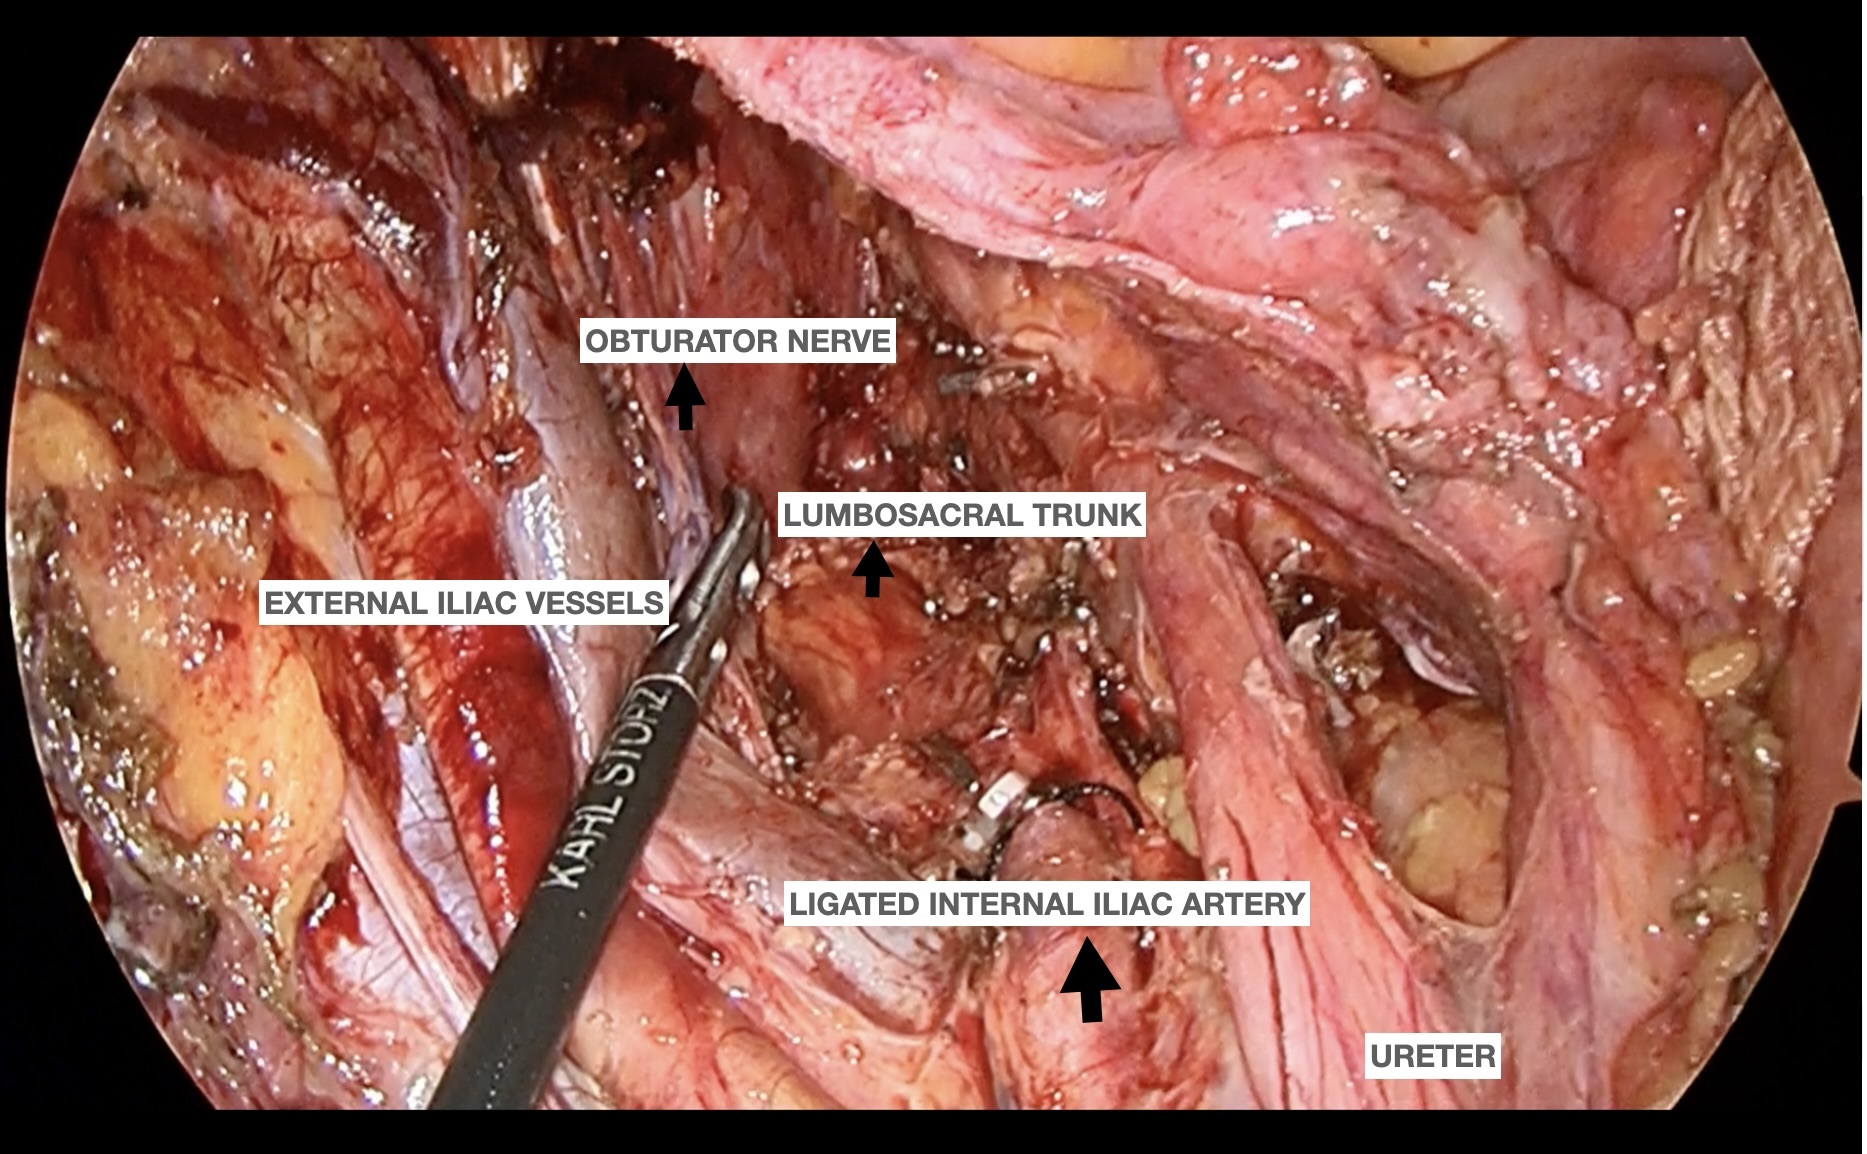

Methods/Interventions: This is a video of a patient undergoing left pelvic node dissection following Simultaneous integrated boost (SIB) radiotherapy to the lateral pelvic node demonstrating the complexity which may arise in such cases. The treatment related changes of neoadjuvant radiation and chemotherapy can lead to edematous tissue planes and extensive fibrosis which needs surgical expertise to ensure optimal oncological outcomes. With the 'Medial Psoas Approach', the external iliac vessels were reflected from lateral to medial aspect from psoas muscle for better delineation and fibrofatty tissue over it was removed from caudal to cranial aspect.This step helped in safely identifying the bifurcation of the common iliac artery, the internal iliac artery and the densely adherent lymph nodal mass. The left internal iliac artery was ligated for better exposure and en block resection of nodal mass which was subsequently dissected from surrounding structures, safeguarding the obturator nerve in posterior aspect. The obliterated umblical artery was ligated and divided and paravesical space dissected, lifting the tissue medial to bladder base .The branches of internal iliac vein encountered are sequentially ligated and divided as we continue to separate from nodal mass.Finally nodal mass is dissected from the levator ani and the lumbosacral trunk located on the floor.

.jpg) Template of Left lateral pelvic node dissection with ligated internal iliac artery

Template of Left lateral pelvic node dissection with ligated internal iliac artery

Methods/Interventions: This is a video of a patient undergoing left pelvic node dissection following Simultaneous integrated boost (SIB) radiotherapy to the lateral pelvic node demonstrating the complexity which may arise in such cases. The treatment related changes of neoadjuvant radiation and chemotherapy can lead to edematous tissue planes and extensive fibrosis which needs surgical expertise to ensure optimal oncological outcomes. With the 'Medial Psoas Approach', the external iliac vessels were reflected from lateral to medial aspect from psoas muscle for better delineation and fibrofatty tissue over it was removed from caudal to cranial aspect.This step helped in safely identifying the bifurcation of the common iliac artery, the internal iliac artery and the densely adherent lymph nodal mass. The left internal iliac artery was ligated for better exposure and en block resection of nodal mass which was subsequently dissected from surrounding structures, safeguarding the obturator nerve in posterior aspect. The obliterated umblical artery was ligated and divided and paravesical space dissected, lifting the tissue medial to bladder base .The branches of internal iliac vein encountered are sequentially ligated and divided as we continue to separate from nodal mass.Finally nodal mass is dissected from the levator ani and the lumbosacral trunk located on the floor.

.jpg) Template of Left lateral pelvic node dissection with ligated internal iliac artery

Template of Left lateral pelvic node dissection with ligated internal iliac artery